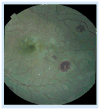

Figure 1. Central and temporal macula showing patchy retinal whitening

Three white-centered hemorrhages are also present.